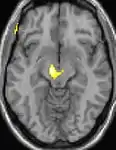

|  |  |  |

| La tomographie par émission de positons (TEP) montre les zones du cerveau étant activées durant la douleur | ||

| La morphométrie voxel par voxel (VBM) montre les différences structurelles des zones du cerveau | ||

Les images par tomographie à émission de positron indiquent les régions du cerveau qui sont activées lors de la douleur, par rapport aux périodes sans douleur. Elles montrent les régions du cerveau qui sont toujours actives durant la douleur en jaune/orange (appelé "matrice-douleur"). La zone au centre (dans les trois vues) est spécifiquement activée uniquement pendant la crise. Les photos sur la ligne du bas (effectuées par VBM) montrent les différences structurelles entre les patients souffrant d'AVF et des personnes saines : seulement une partie de l'hypothalamus est différente[50],[51].